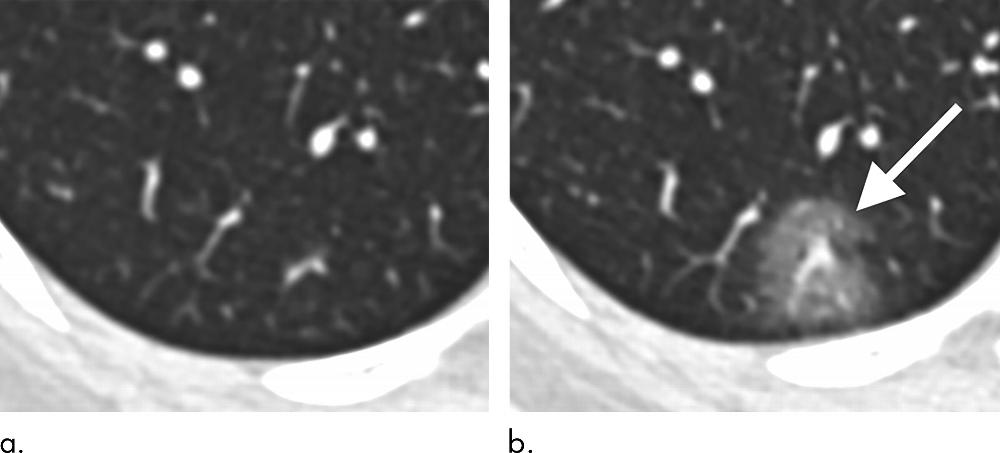

Figure 5. 43-year old female with a history of travel to Wuhan presenting with fever. (a) Axial thin-section non-contrast CT image from 1/18/2020 shows normal lung. (b) Follow-up CT image from 1/21/2020 shows a new solitary, rounded, peripheral ground-glass lesion in the right lower lobe (arrow).

“Our patient population is unique from other published series on the Wuhan coronavirus in that three of our patients had normal initial chest CTs,” he said. “One of these patients progressed three days later and developed a solitary nodular ground-glass lesion in the right lower lobe, indicating this pattern may represent the very first radiologically visible manifestation of disease in some patients infected with Wuhan coronavirus.”